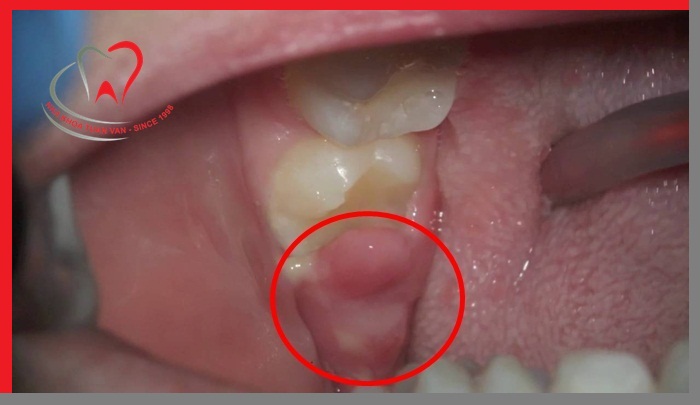

Viêm lợi chùm gây đau đớn, khó chịu

- Phần lợi bị sưng phồng lên, có màu đỏ, che lấp mặt răng tạo thành một vạt nướu trùm lên răng khôn.

- Sưng lợi trong cùng luôn khiến bệnh nhân khó há miệng, đặc biệt trong quá trình ăn uống và giao tiếp.

- Nếu bệnh phát triển có thể làm cho người bệnh đau nhức, phát sốt, cơ thể mệt mỏi, khó chịu và nổi hạch ở cổ.